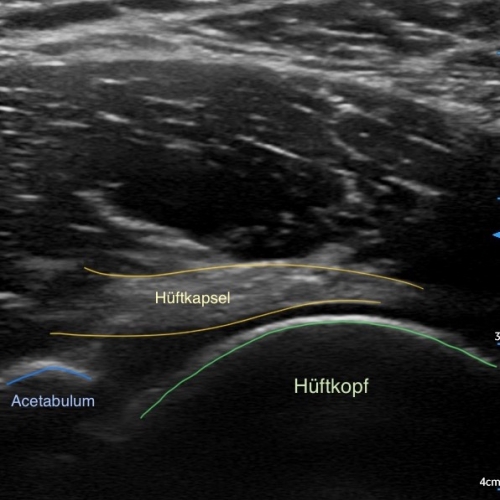

Hierbei werden akustische Wellen (hochfrequente mechanische Schwingungen) durch den Körper geleitet und anschließend von unterschiedlichen Gewebetypen unterschiedlich stark reflektiert. Dies wird dann in ein Bild umgewandelt. Mit entsprechenden Geräten und Wissen lassen sich so viele Diagnosen bestätigen oder ausschließen, angefangen von Muskel- und Bandverletzungen, über Knochenveränderungen bis hin zu Flüssigkeitsansammlungen.

Auch im Rahmen der SPORTMEDIZIN und INJEKTIONSTHERAPIE ist das Sonographiegerät eine tolle Ergänzung. Liegt zum Beispiel ein Muskelfaserriss vor, so kann dieser nicht nur dargestellt und dokumentiert werden, sondern jetzt auch unter Kontrolle ganz gezielt eine Injektion im defekten Bereich gesetzt werden. Auch bei Injektionen an Gelenken wird die Treffsicherheit massiv gesteigert.